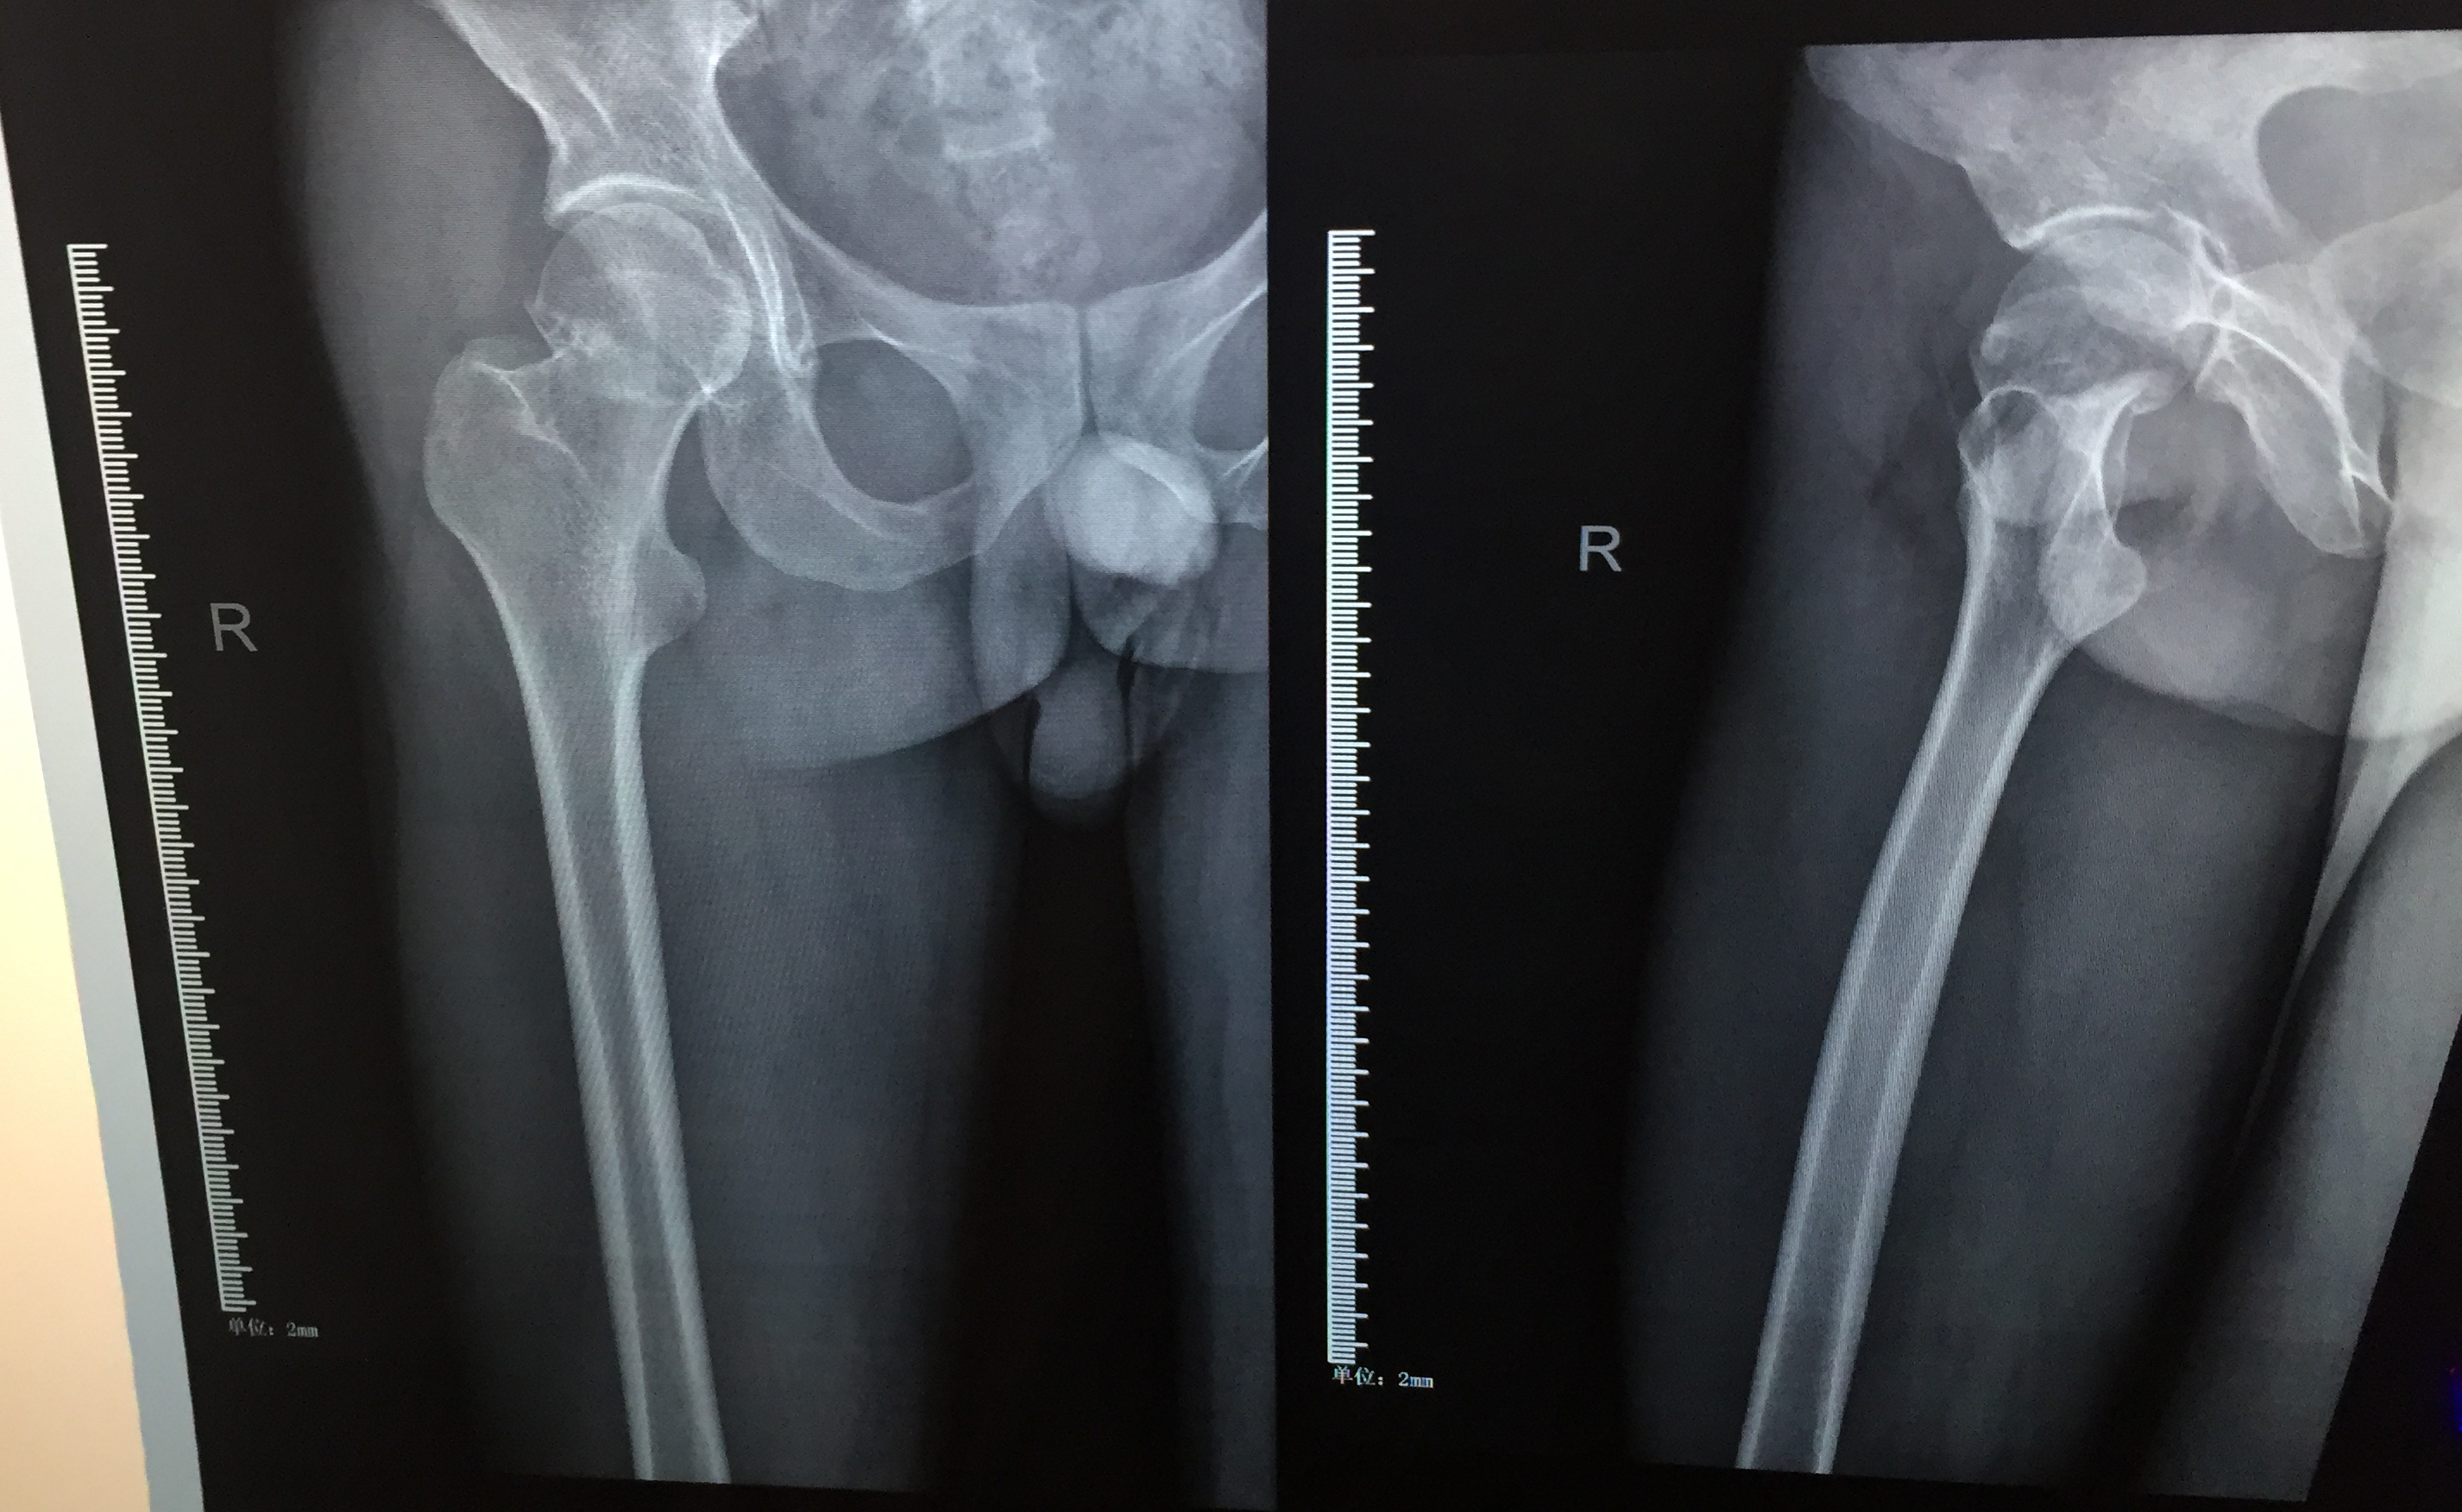

这是我家人的X光和CT照片,目前在住院,下周一手术。请懂得吧友帮忙看看,这个是头下型吗?有多严重?

头下,有些移位!准备打好持久战

回复 落云沥泉 :还好,移位不大!还好啦,看手术复位!

头下嵌插,应该属于一型,嵌插属于稳定型骨折,算是轻的。

头下三 ,挺严重,好好躺着修养吧

嵌插型 最多头二 属于稳定型股骨颈骨折 不要过于担心